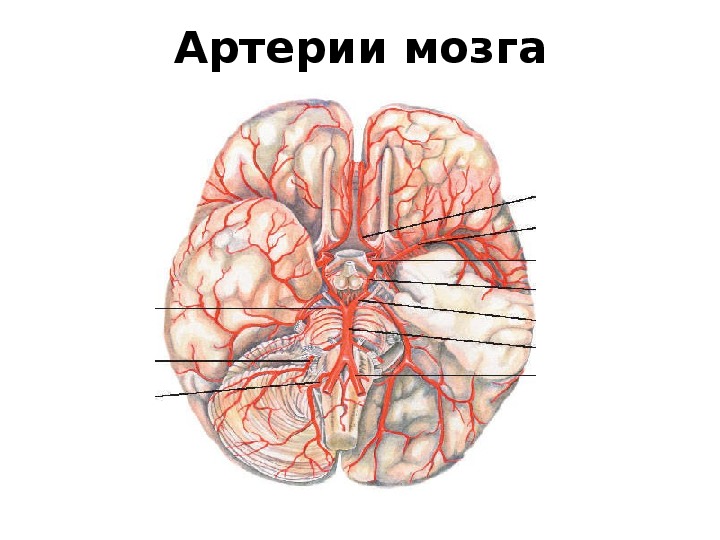

Анатомия: Задняя соединительная артерия мозга